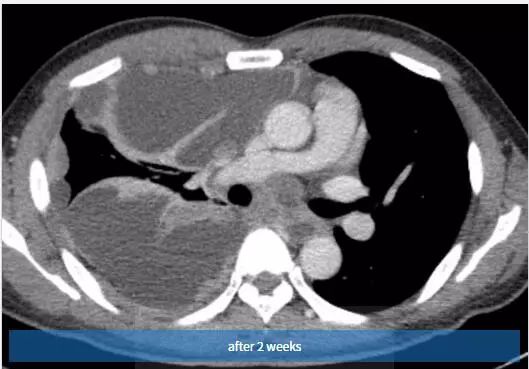

图4~6 2周内随访的对比增强轴位CT扫描示右半胸有大量多发性胸腔积液,弥漫性胸膜增厚和多灶性胸膜肿块。

诊断:Askin 瘤